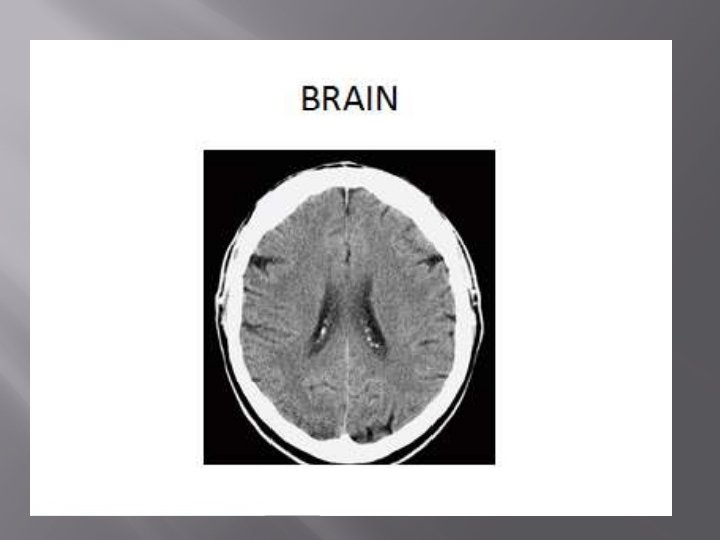

� A computerized tomography (CT) scan combines a series of X-ray images taken from different angles around your body and uses computer processing to create cross-sectional images (slices) of the bones, blood vessels and soft tissues inside your body. CT scan images provide more-detailed information than plain Xrays do.